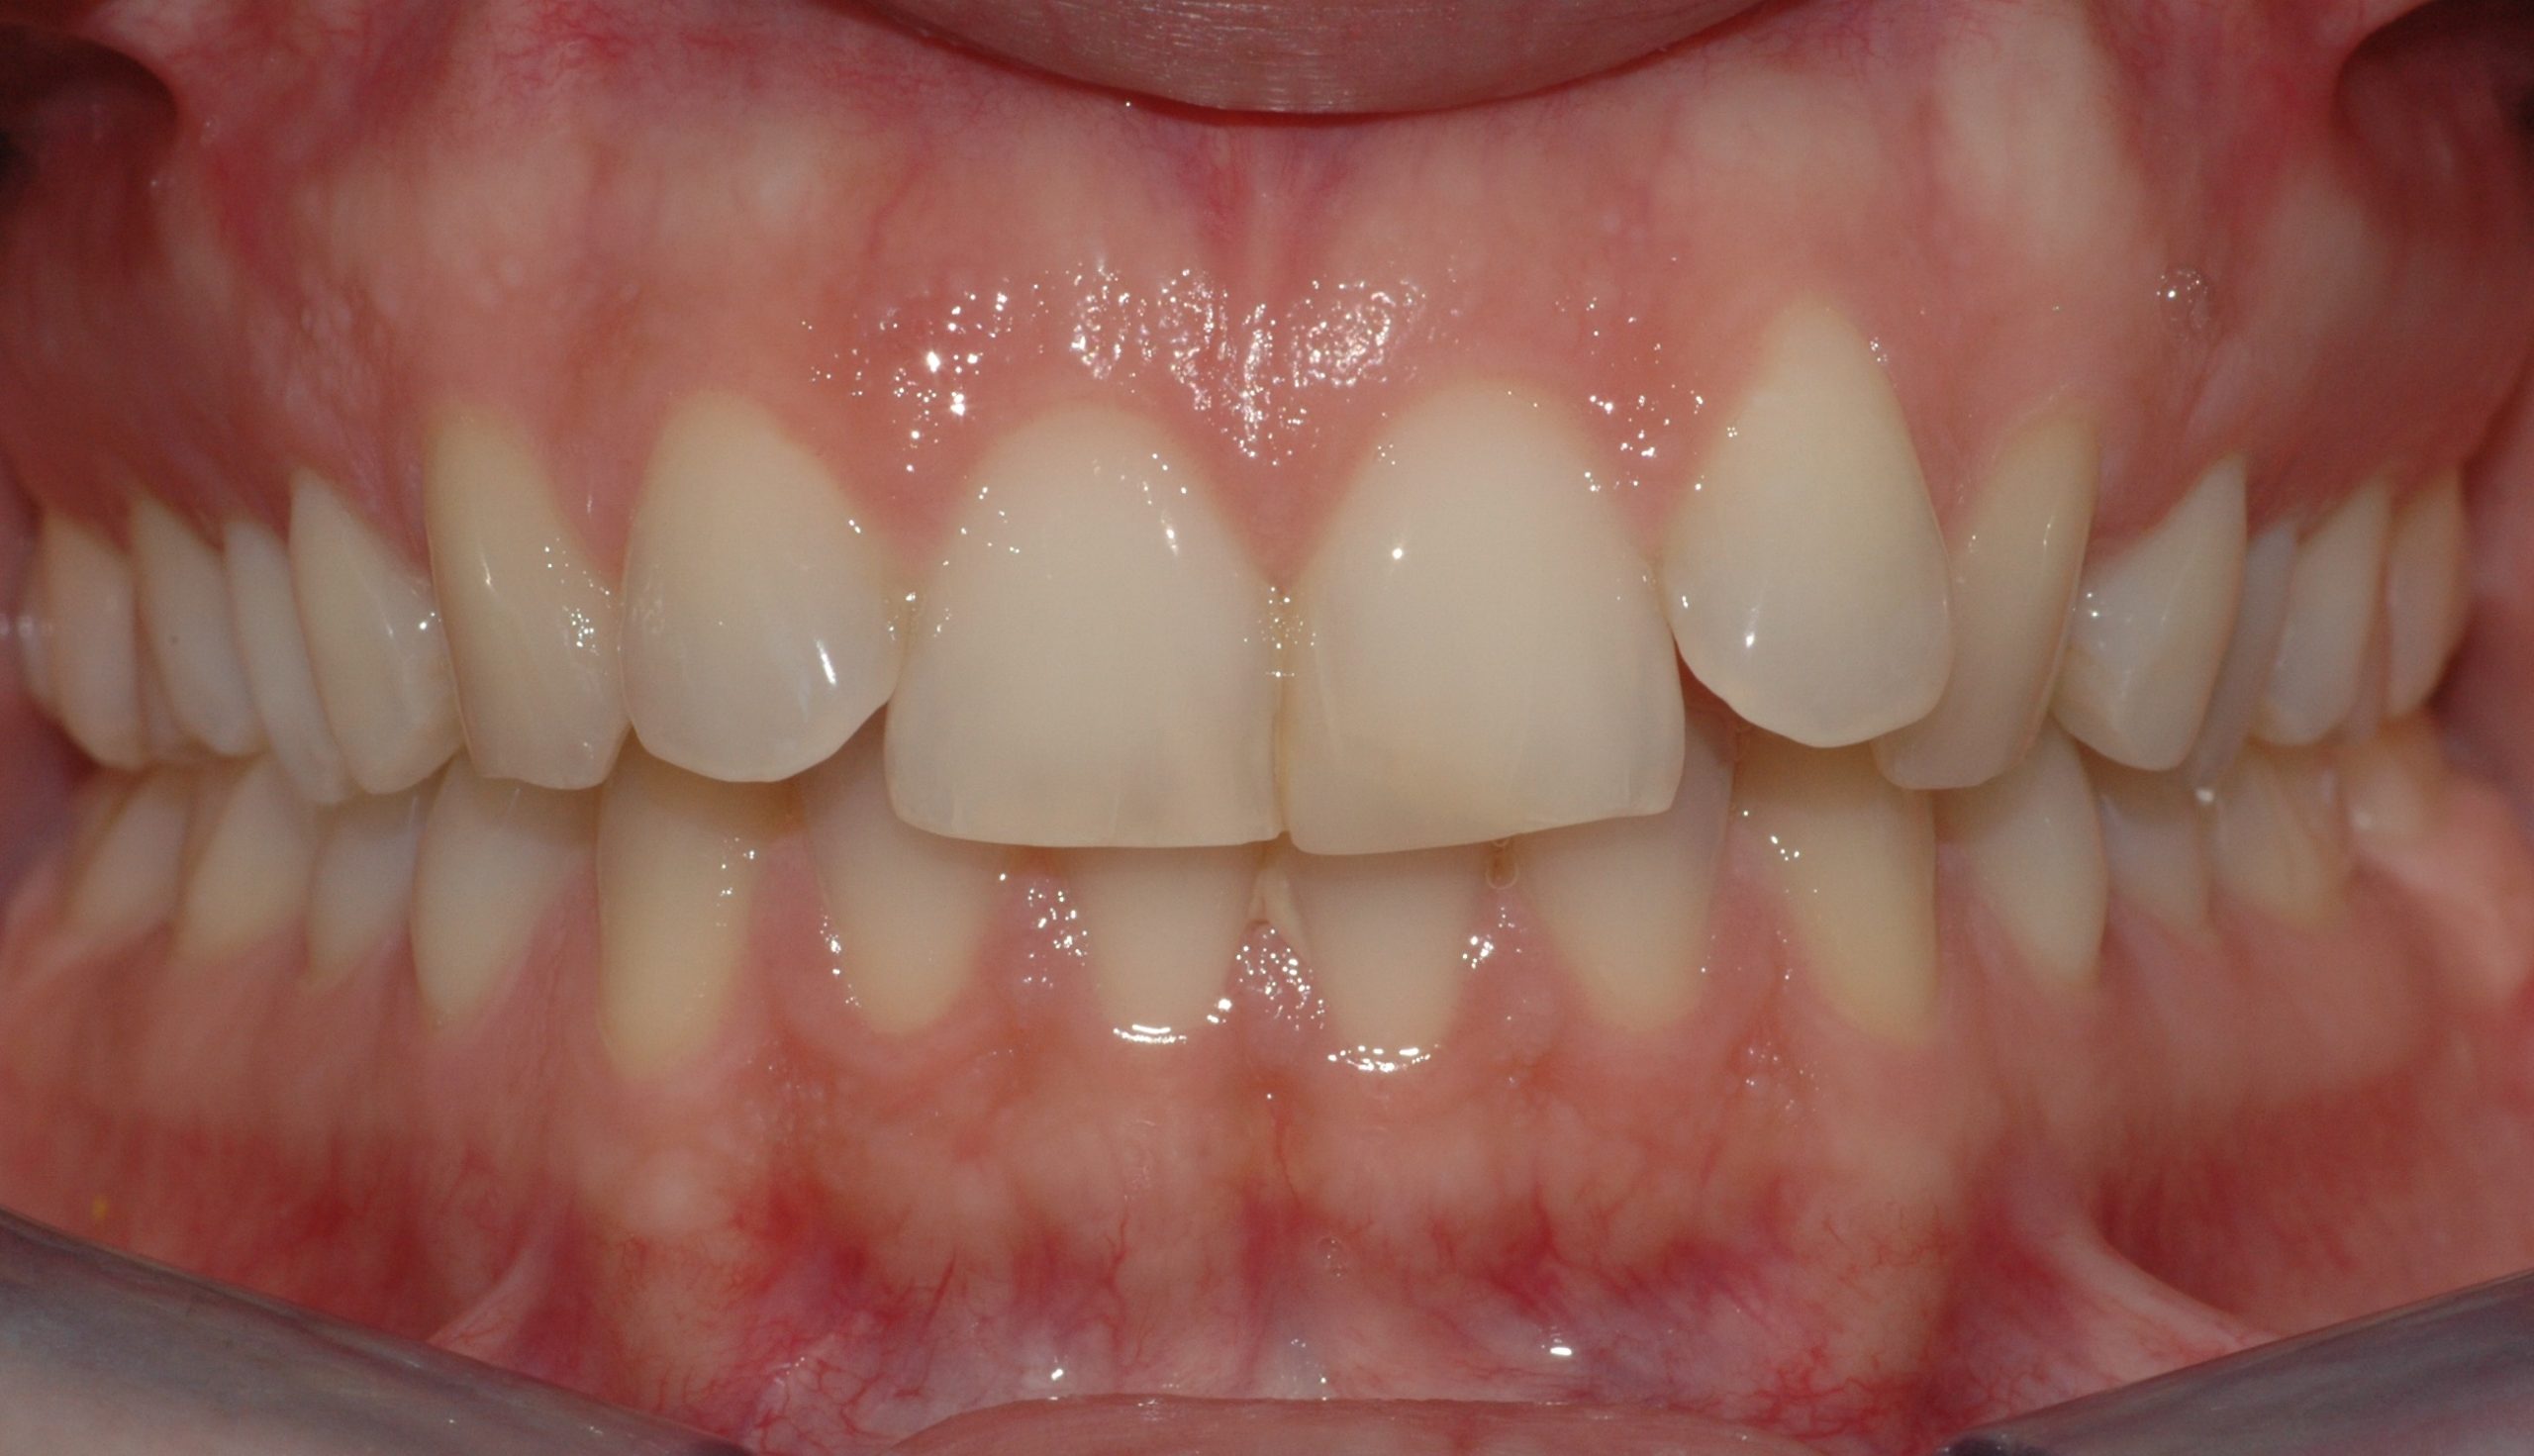

Caso clinico

La paziente si presenta a causa del malposizionamento del canino superiore di sinistra, ruotato lungo il suo asse di quasi 90 gradi. In seguito ad un trattamento con allineatori trasparenti di circa 7 mesi, il dente è stato portato in posizione assolutamente idonea.